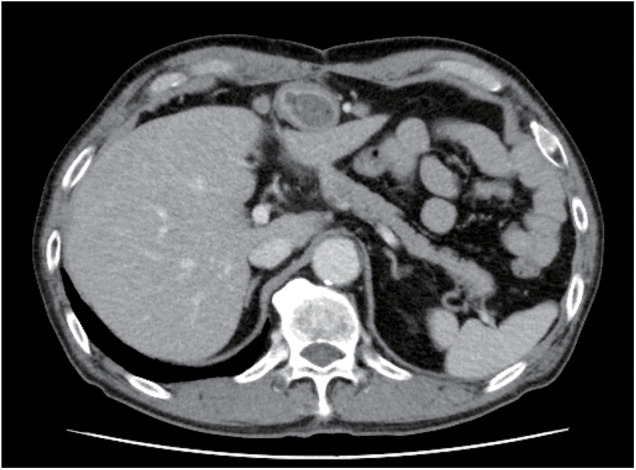

The incidence of gastric tube cancers has increased due to improved survival rates in patients after esophagectomy. However, the optimal surgical approach for gastric tube cancer remains controversial. Here, we report the case of a 70-year-old man with advanced gastric cancer arising from a retrosternally placed gastric conduit, 12 years after thoracic esophagectomy for esophageal cancer. Total resection of the gastric conduit was performed with robotic assistance. Although the working space was limited, secure resection was possible. Continuous en bloc mobilization was achieved with neck dissection, and reconstruction was performed via the same retrosternal route using the ileocolon. The patient was discharged on the 14th postoperative day without any adverse events. Robot-assisted surgery can overcome the technical limitations of laparoscopic mediastinal surgery and has advantages such as improved ergonomics, comfort, and elimination of hand tremors, and therefore may be an option for future minimally invasive surgeries.